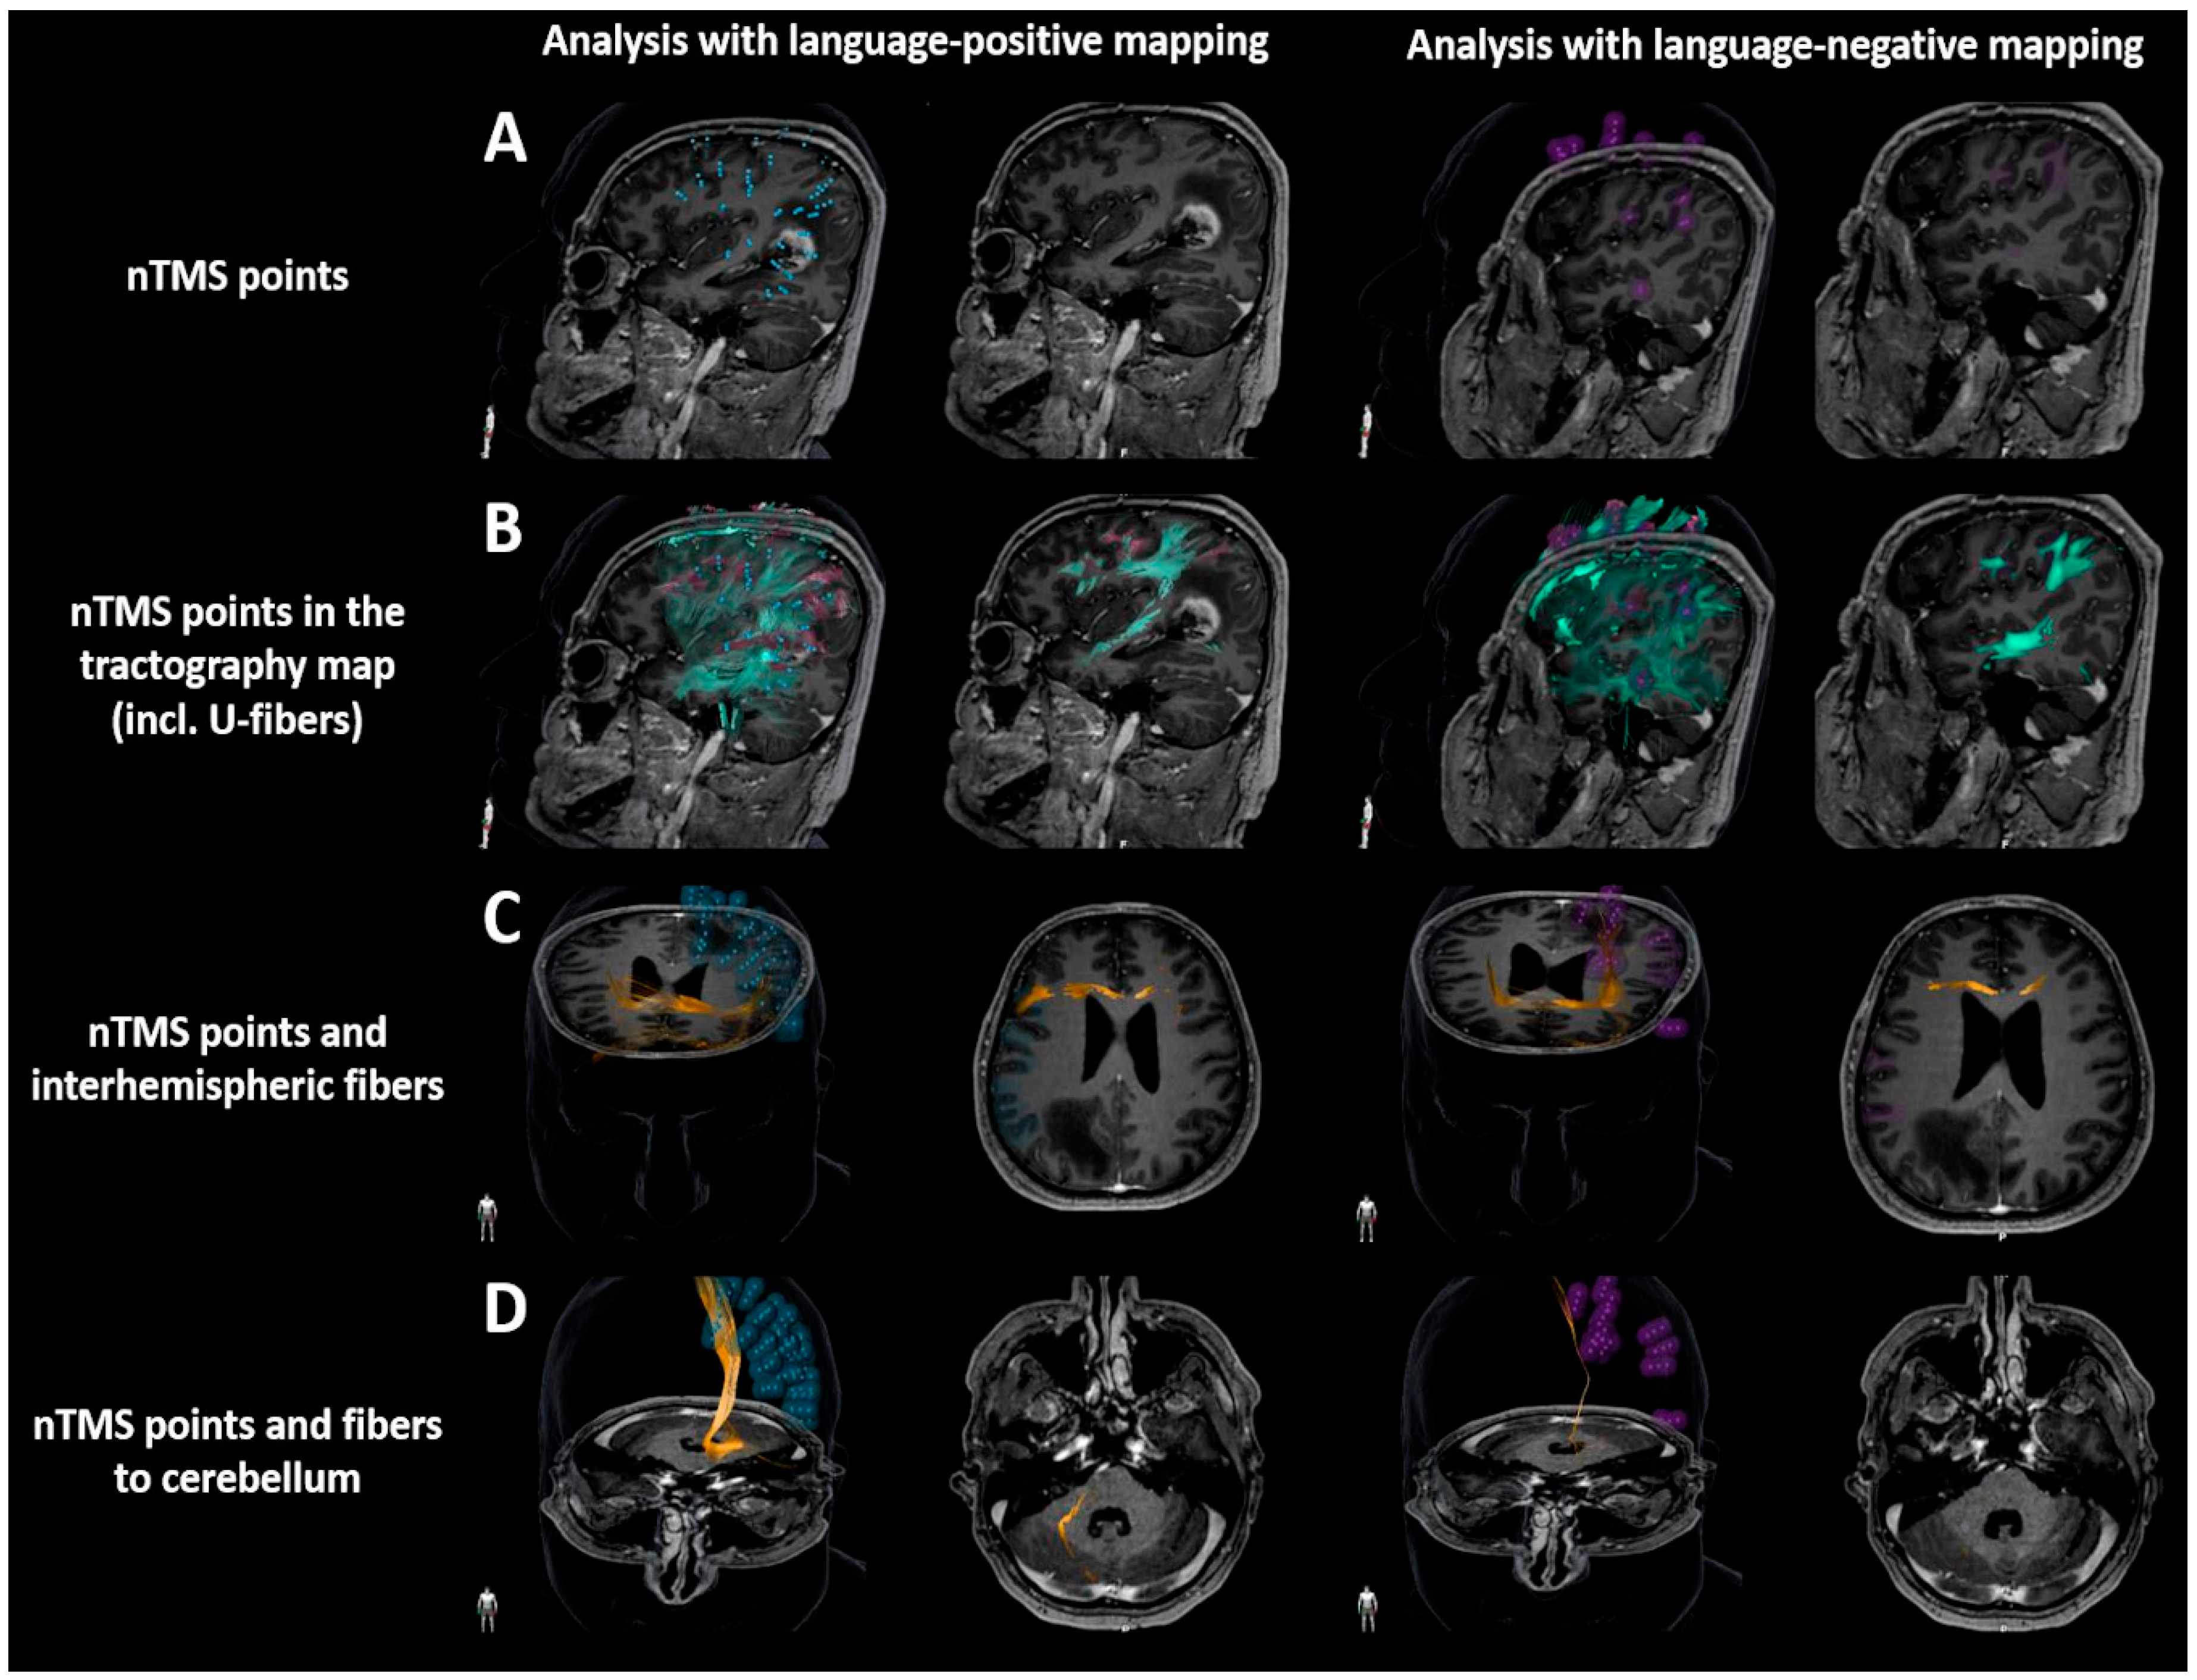

2.7.2. U-Fibers

2.7.3. Interhemispheric Fibers and Fibers Projecting to the Cerebellum

3.2. Comparison between Language-Positive and Language-Negative Mapping and Tractography

3.3. Associations with Aphasia Grading